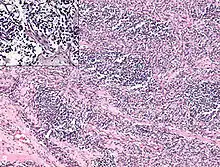

It is generally considered to be a disease of childhood, as the vast majority of cases occur in those below the age of 18. It is commonly described as one of the small-blue-round-cell tumors of childhood due to its appearance on an H&E stain.[4] Despite being relatively rare, it accounts for approximately 40% of all recorded soft tissue sarcomas.[5][6][7]

Rhabdomyosarcoma is often difficult to diagnose due to its similarities to other cancers and varying levels of differentiation. It is loosely classified as one of the small-blue-round-cell tumors due to its appearance on an H&E stain. Other cancers that share this classification include neuroblastoma, Ewing sarcoma, and lymphoma, and a diagnosis of RMS requires confident elimination of these morphologically similar diseases.[14] The defining diagnostic trait for RMS is confirmation of malignant skeletal muscle differentiation with myogenesis (presenting as a plump, pink cytoplasm) under light microscopy.[5] Cross striations may or may not be present. Accurate diagnosis is usually accomplished through immunohistochemical staining for muscle-specific proteins such as myogenin, muscle-specific actin, desmin, D-myosin, and myoD1.[25][34][35] Myogenin, in particular, has been shown to be highly specific to RMS,[36] although the diagnostic significance of each protein marker may vary depending on the type and location of the malignant cells. The alveolar type of RMS tends to have stronger muscle-specific protein staining. Electron microscopy may also aid in diagnosis, with the presence of actin and myosin or Z bands pointing to a positive diagnosis of RMS.[5][34] Classification into types and subtypes is accomplished through further analysis of cellular morphology (alveolar spacings, presence of cambium layer, aneuploidy, etc.) as well as genetic sequencing of tumor cells. Some genetic markers, such as the PAX3-FKHR fusion gene expression in alveolar RMS, can aid in diagnosis. Open biopsy is usually required to obtain sufficient tissue for accurate diagnosis. All findings must be considered in context, as no one trait is a definitive indicator for RMS.